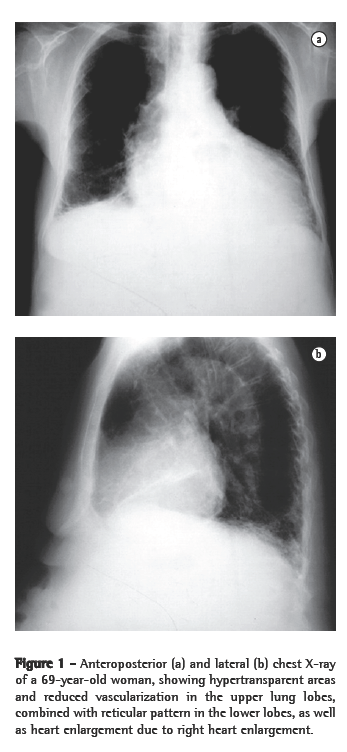

On chest X-rays and HRCT scans, all patients presented findings consistent with emphysema and IPF (Figures 1 and 2). Radiotransparent areas were seen in the upper lobes on X-rays in all cases. Reticular opacities were present in the lung bases in 6 cases. All but 2 patients presented honeycombing. Areas of attenuation appeared as ground-glass opacities in 4 cases. Traction bronchiectasis was described in 3 of the 11 cases. Of the total number of patients in this study, 5 presented a PaO2 < 70 mmHg at rest, which was determined by arterial blood gas analysis on room air. The mean pH, arterial carbon dioxide tension, bicarbonate, PaO2, and arterial oxygen saturation were 7.44 ± 0.03, 32.8 ± 6.7 mmHg, 21.5 ± 3.6 mmol/L, 68.9 ± 11.9 mmHg, and 94.2% ± 3.3%, respectively. None of the patients presented hypercapnia.

In this study, we have reported clinical and functional findings in 11 patients who presented, simultaneously, emphysema in the upper lung lobes and fibrosis in the lower lung lobes, resulting in a mixed pattern in pulmonary function tests. In the concomitance between these two diseases, FEV1 and FEV1/FVC ratio can be normal or consistent with mild obstruction or restriction, with relatively preserved pulmonary volumes and a significant decrease in DLCO. In such patients, PH and hypoxemia can occur at rest or upon exertion.